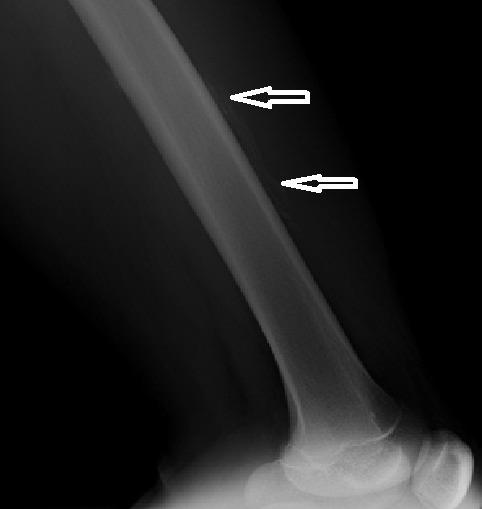

[Epidemiological, clinical and radiological profile of musculoskeletal disorders of hemophiliacs in Madagascar].

Pan Afr Med J. 2014 Nov 15;19:287. doi: 10.11604/pamj.2014.19.287.5237. eCollection 2014.